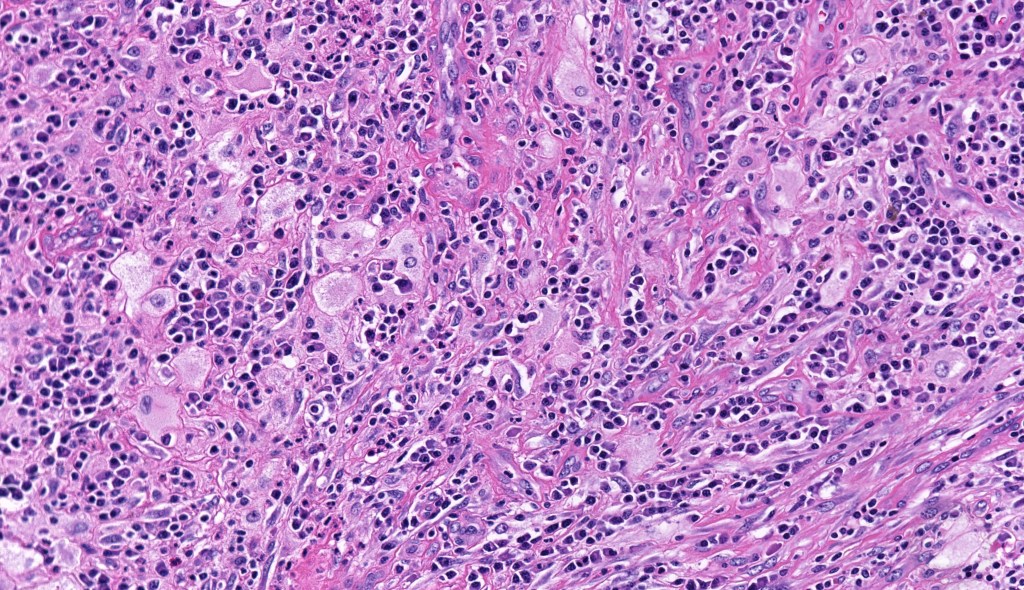

•Due to the admixture of pale histiocytes and lymphocytes, the scanning view is characteristic, and the diagnosis can be strongly suspected at this magnification

•Dense dermal nodular infiltrate sometimes extending into subcutaneous fat

•Histiocytes are large with irregular borders and abundant cytoplasm

• Vesicular nuclei with a prominent nucleoli

•Emperipolesis of lymphocytes, plasma cells & neutrophils

•Background population of lymphocytes, plasma cells, neutrophils, eosinophils & variable numbers of xanthoma cells